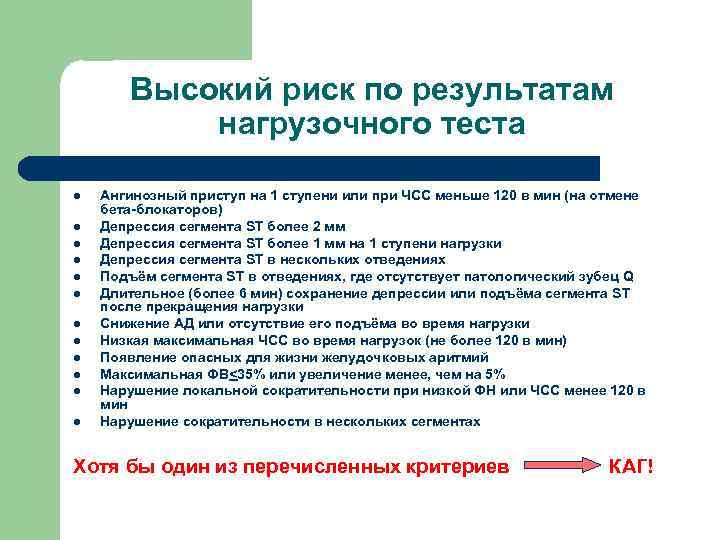

Высокий риск по результатам нагрузочного теста l l l Ангинозный приступ на 1 ступени или при ЧСС меньше 120 в мин (на отмене бета-блокаторов) Депрессия сегмента ST более 2 мм Депрессия сегмента ST более 1 мм на 1 ступени нагрузки Депрессия сегмента ST в нескольких отведениях Подъём сегмента ST в отведениях, где отсутствует патологический зубец Q Длительное (более 6 мин) сохранение депрессии или подъёма сегмента ST после прекращения нагрузки Снижение АД или отсутствие его подъёма во время нагрузки Низкая максимальная ЧСС во время нагрузок (не более 120 в мин) Появление опасных для жизни желудочковых аритмий Максимальная ФВ<35% или увеличение менее, чем на 5% Нарушение локальной сократительности при низкой ФН или ЧСС менее 120 в мин Нарушение сократительности в нескольких сегментах Хотя бы один из перечисленных критериев КАГ!